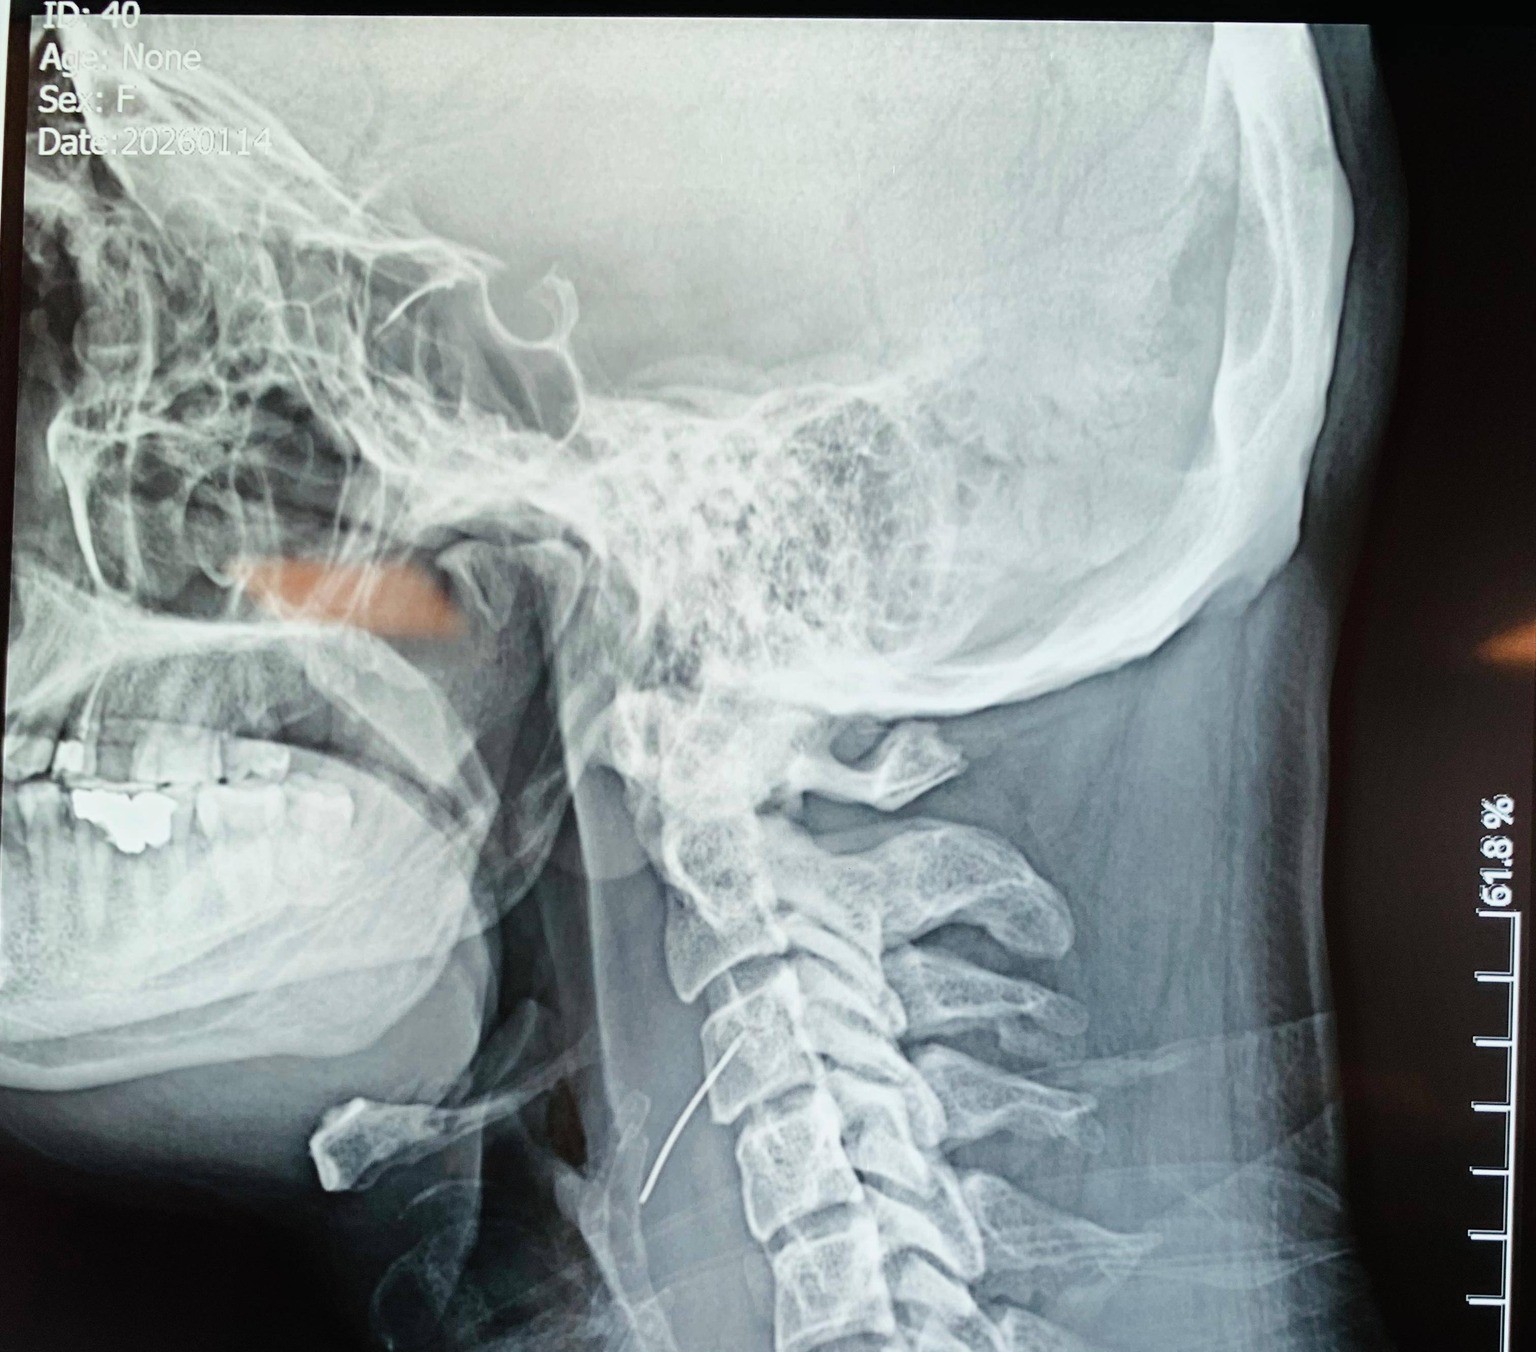

هاووڵاتییەكی تەمەن 42 ساڵ سەردانی نەخۆشخانەی فریاكەوتنی ڕانیەی كرد و باسی لەوەكرد دوای ئەوەی ژەمێك مریشكی خواردووە هەست دەكات گیربوونێك لە قوڕگیدا هەیە و ڕێكاری تەندروستی پێویستی بۆ كرا و ڕەوانەی نەخۆشخانەی شار لە سلێمانی كرا.

لە نەخۆشخانەی شار دوای ئەوەی پزیشكەكان دڵنیابوون لە گیربوونی تەنێكی نامۆ لە بەشی خوارەوەی قوڕگی نەخۆشەكە و نزیكبوونەوەی لە فەقەراتی ملی ، بە پەلە نەشتەرگەرییان بۆ ئەنجامدا و دەرزییەكی 3.5 سم لە قوڕگی نەخۆشخەكە دەرهێنا و مەترسییەكی گەورە لەسەر ژیانی لابرا ، كە بەوتەی خۆی دەرزییەكە لەناو ئەو مریشكەدا بووە كە خواردوویەتی.